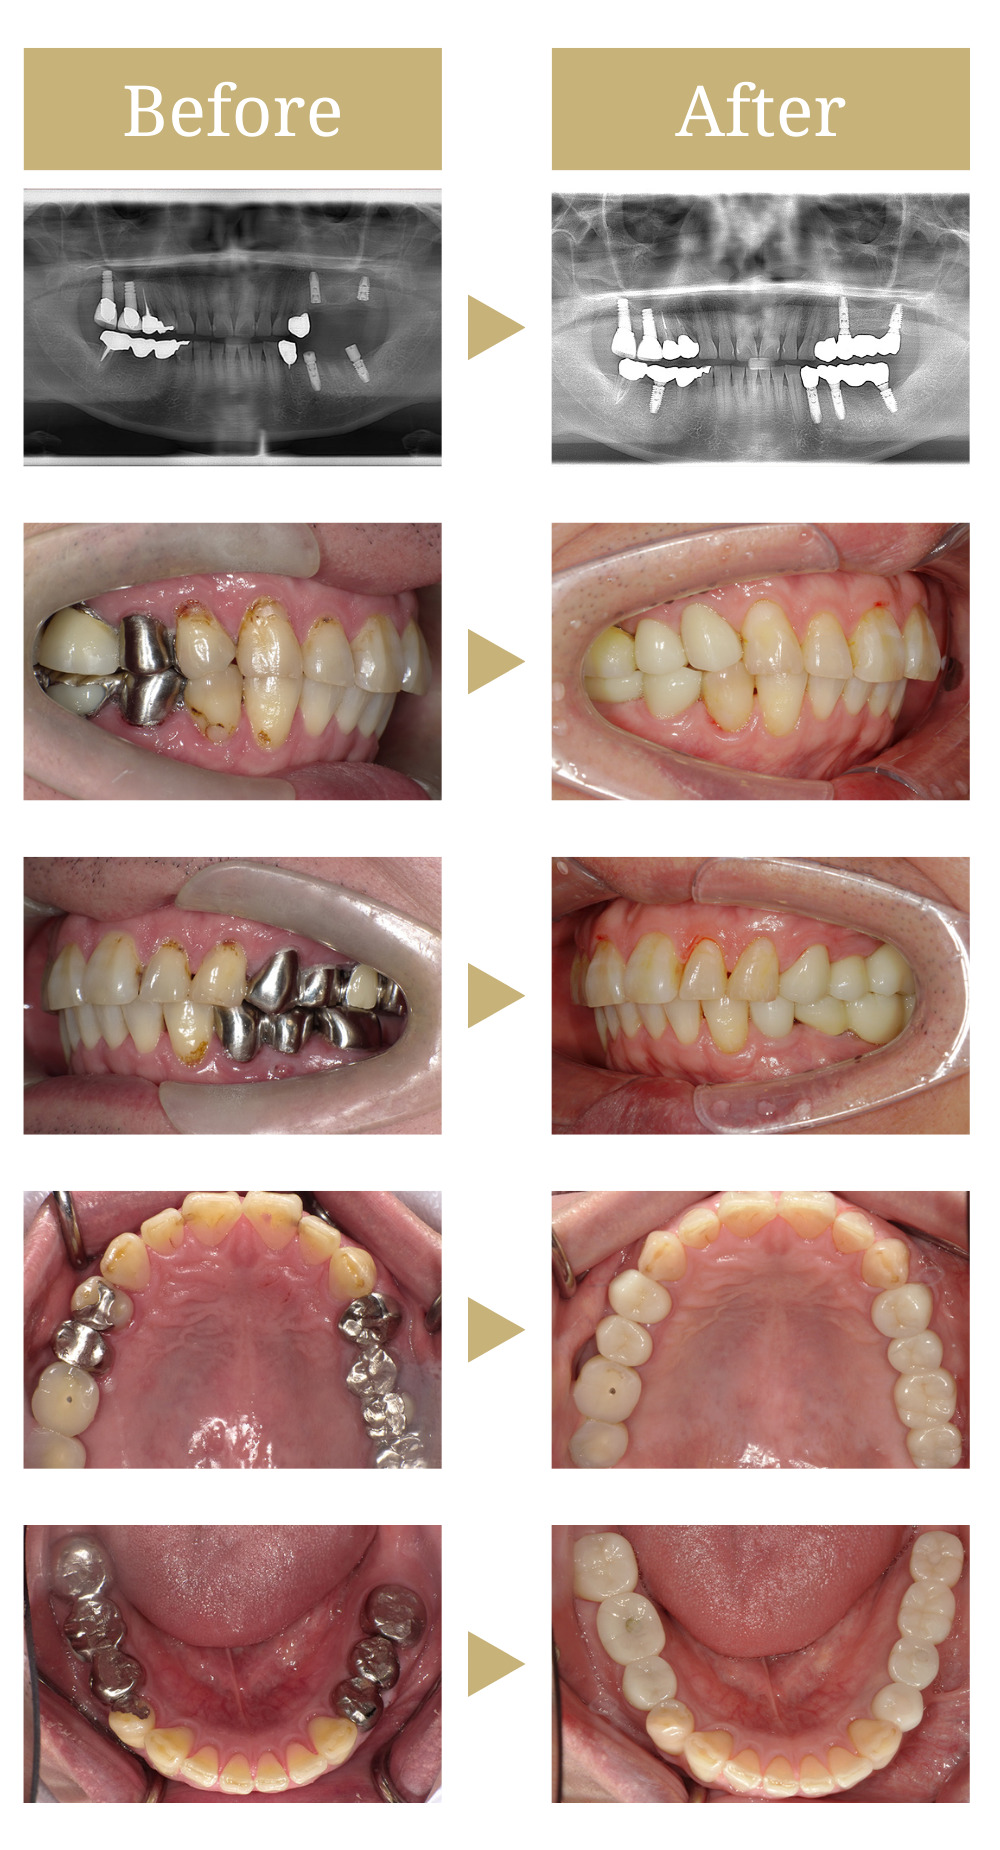

インプラント治療で負担の少ないバランスの良い噛み合わせを作る

奥歯欠損と噛み合わせ不良

奥歯の調子が悪く、インプラント治療を検討。他、全顎的な治療を希望とのことでご来院されました。

当院からは、まず破折している歯を抜歯し、その後インプラント治療を行うことを提案しました。また、虫歯が進行している前歯については、患者様から見た目が気になるとのご希望を受けて、審美治療を提案しました。